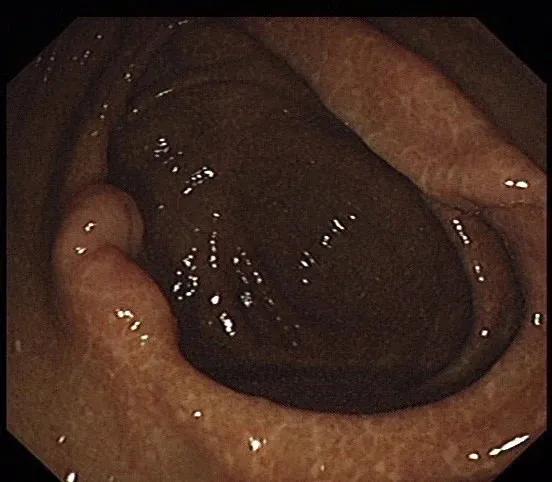

傅传刚教授随后为王先生安排了肠镜:结肠镜插入至肝区,结肠冗长迂曲,进镜困难,所见横结肠,降结肠,乙状结肠及直肠粘膜光滑,见色素沉着,余未见异常。诊断:中度结肠黑变病 结肠冗长迂曲。